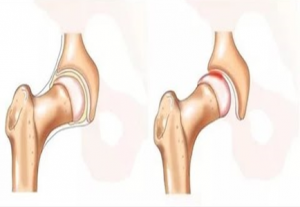

Анатомо-физиологиялық ерекшеліктері. Сан диафизі мықты бұлшықеттермен қоршалған және қанмен жақсы қамтамасыз етіледі, бұл бір жағынан сынық кезіндегі тінішілік қан кетуді анықтаса, екінші жағынан тез бітісуге де жақсы.

Доминирлеуші бұлшықет қатаюының реализациясы, жоғарғы үштен бір бөлігіндегі бұлшықеттер сынық кезінде проксимальды сынықшаның бүгіліп, әкетілуіне және сыртқы ротациясына әкеледі, ал дистальды сынықша ішке және әкелетін бұлшықеттер тартуынан жоғары ығысады. Сонымен қатар, сынық неғұрлым жоғары болса, соғұрлым проксимальды сынықшаның сыртқа ығысуы болады. Санның ортаңғы үштен бір бөлігінің сынықтарында бұлшықеттер антогонисттері арқасында сынықшалардың көлденең және ұзыннан ығысуына және айқын емес ось деформациясына әкеледі.

Диафиздің төменгі үштен бір бөлігінің сынығына балтыр бұлшықетінің жиырылуынан дистальды сынықшаның артқа ығысуы болады. Тізе асты артериясы қоса зақымдалуы мүмкін. Проксимальды сынықша әкелетін бұлшықеттер салдарынан ішке ығысады